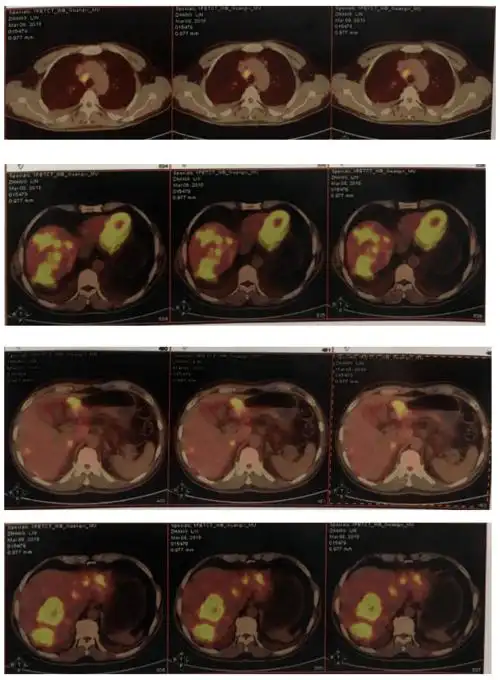

例精图治丨及时准确检测合理抗her2治疗助力胃癌晚期患者达更长os